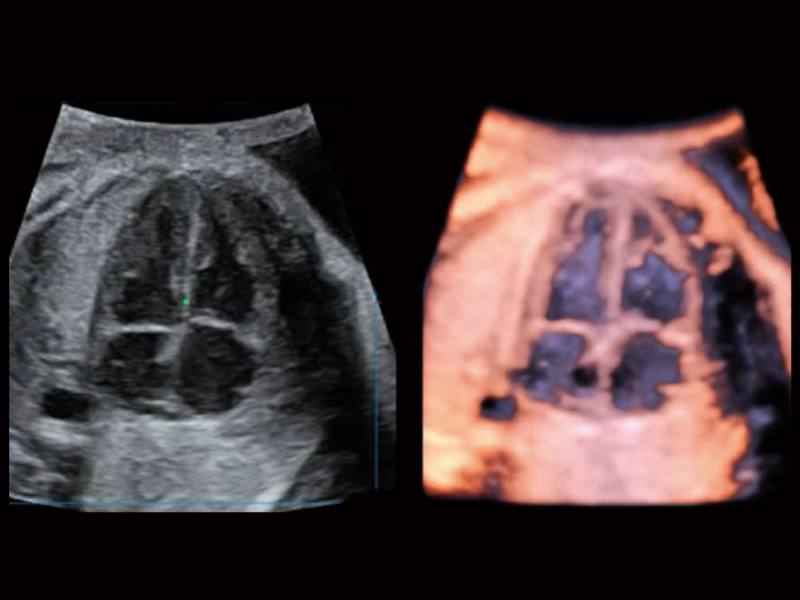

丰富的血流动力学检测技术,可在不同医疗场景中高效捕捉血流信号,助力临床诊疗。

在传统血流的基础上优化扫查和算法策略,能够更好的抑制组织信息,提炼红细胞运动信息,得到更高帧频,高灵敏度和分辨率的血流信号,还原更真实的血流动力学。

通过光照模型,使二维血流显示出立体的效果,增加血流的敏感性、成束性,减少外溢。可以和其他不同的血流技术联合使用,融合不同技术的优势。轻松应对微小血管,增强血流的立体效果,提升视觉敏感性。